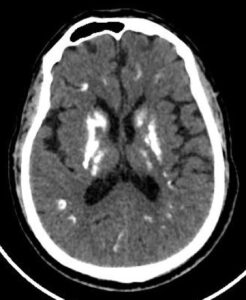

CASE 6- FAHR’S DISEASE

Near symmetric patchy calcifications are seen in bilateral cerebral and cerebellar hemispheres including:

- Bilateral basal ganglia

- Thalami

- Dentate nuclei

- Bilateral corona radiata.